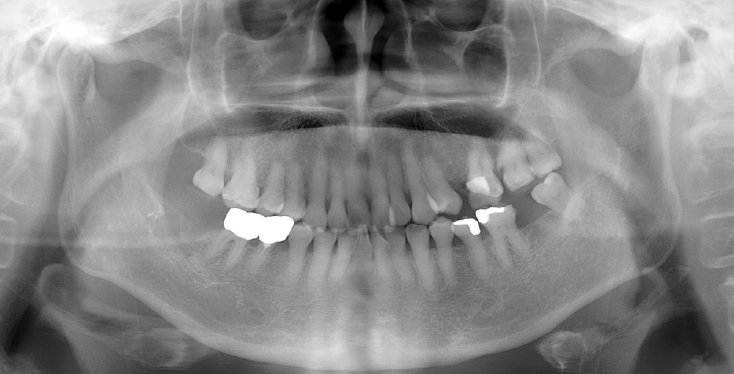

An 18-year-old male developed numbness in the right lower lip, gingiva, and chin following endodontic treatment of the mandibular right first molar (#46) at a military hospital 2 weeks ago. A panoramic radiograph and multi-detector computed tomography (MDCT) revealed extruded Calcipex II in proximity to the IAN (Fig. 6). Neurologic testing confirmed severe hypoesthesia in the right mentum region. Thermal discrimination was absent across a broad area of the right lower lip and chin. The patient’s subjective discomfort was rated as VAS 2. The patient underwent foreign body removal, nerve transposition, and bone grafting under general anesthesia (Fig. 7). At one-week postoperative follow-up, neurosensory testing showed little to no improvement. At the five-month follow-up, repeated neurosensory testing demonstrated meaningful improvement in directional discrimination and pin-pressure nociceptive discrimination, despite the continued presence of hypoesthesia. At the 17-month follow-up, testing revealed further improvement, including recovery of static light touch sensation, with overall symptoms classified as mild hypoesthesia. However, the patient reported worsening subjective discomfort, with a VAS 5, reflecting a discordance between objective sensory recovery and subjective symptom persistence.- Case 5